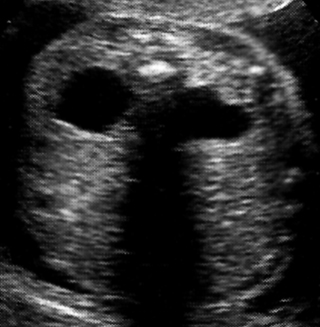

Πλειοκυστική δυσπλασία

(Potter II)

Πρόκειται για ανωμαλία που συναντάται σε 1 στις 1.000 γεννήσεις, ενώ στις μισές

περιπτώσεις συνδέεται με χρωμοσωμικές ανωμαλίες, γενετικά σύνδρομα και άλλες

διαμαρτίες (κυρίως καρδιακές).

Υπερηχογραφικά, οι νεφροί απεικονίζονται με πολλαπλές κύστεις ποικίλου μεγέθους,

που δεν επικοινωνούν μεταξύ τους και υπερηχογενές στρώμα (εικόνες 6, 7).

Η διάμετρος των κύστεων καθορίζει και το τελικό μέγεθος των νεφρών, που μπορεί

να είναι μεγάλο, όπως στον τύπο ΙΙa, ή μικρό, όπως στον τύπο ΙΙb. Μπορεί να

είναι αμφοτερόπλευρη, ετερόπλευρη ή να αφορά σε ένα τμήμα του νεφρού. Στην αμφοτερόπευρη

νόσο, συνυπάρχει ανυδράμνιο και η ουροδόχος κύστη είναι απούσα.

Όταν πρόκειται για αμφοτερόπλευρη νόσο, η πρόγνωση είναι μοιραία, ενώ στη μονόπλευρη

νόσο, η πρόγνωση είναι καλή (αν και σε ένα μεγάλο ποσοστό συνυπάρχουν και άλλες

ουρογεννητικές ανωμαλίες). Υπάρχει διχογνωμία απόψεων σχετικά με τη προφυλακτική

νεφρεκτομή, ενώ η πλειοψηφία των ουρολόγων υιοθετεί τη συντηρητική αντιμετώπιση,

καθώς ο προσβεβλημένος νεφρός υποστρέφεται και μπορεί να εξαφανισθεί.

Εικόνα 6. Potter II, εγκάρσια διατομή. |

| Εικόνα 7. Potter II, επιμήκης διατομή. | Εικόνα 8. Potter III. | Εικόνα 9. Potter III, εγκάρσια διατομή επιμήκης διατομή. |